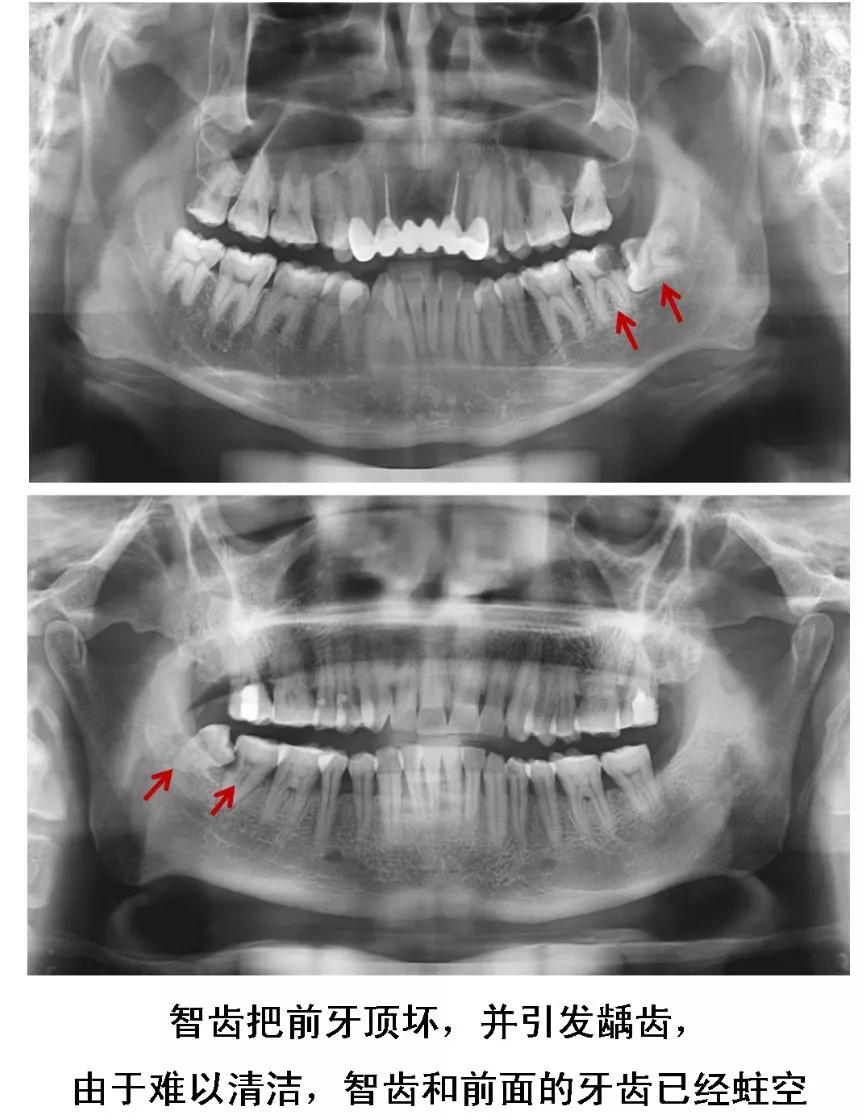

2、长歪的阻生智齿

当智齿没有足够空间生长,脱离“轨道”,与邻牙之间产生缝隙,容易嵌塞食物,滋生细菌,引起蛀牙。

或是智齿生长的方向正好顶住邻牙,时间久了不仅会把邻牙顶坏,龋坏进一步发展会造成牙髓炎。